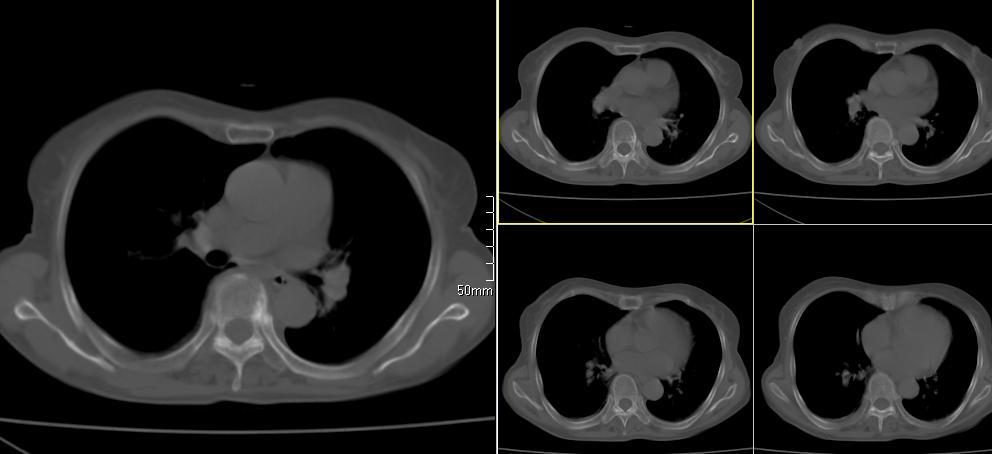

标题: CT26857:女,60岁,胃部不适前来就诊,不咳嗽,乏力,胸椎 [打印本页]

标题: CT26857:女,60岁,胃部不适前来就诊,不咳嗽,乏力,胸椎

1、胸椎有骨质破坏伴周软组织,考虑胸椎转移。2、考虑左肺上叶尖后段支气管开口区周围型肺癌可能。

1、胸椎有骨质破坏伴周软组织,考虑胸椎转移。2、考虑左肺上叶尖后段支气管开口区周围型肺癌可能。建议行纤支镜检查!

1、胸椎有骨质破坏伴周软组织,考虑胸椎转移。2、考虑左肺中央型肺癌可能。

支持中央型肺癌,胸椎转移。

1)考虑左肺中央型肺癌。2)胸椎转移瘤不排除;建议行mri检查。